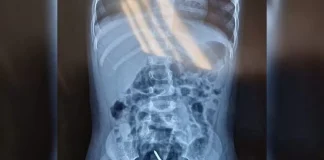

Parafusos são encontrados dentro de bebê de 1 ano; pai é...